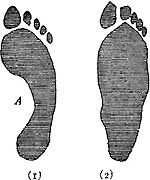

230 Imprint of (1) Arched Foot and (2) Flat Foot

231 The Result of Wearing a Fashionable Shoe